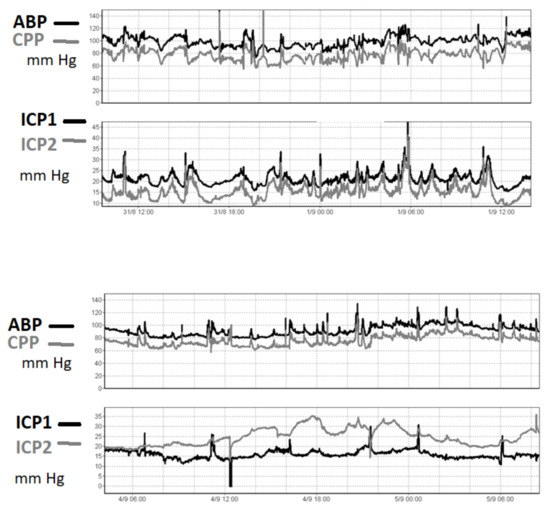

3.3. Comparing ICP Sensor Performance to Bench Testing

4.3. Agreement between Intraparenchymal Sensors and CSF Pressure in Clinical Studies